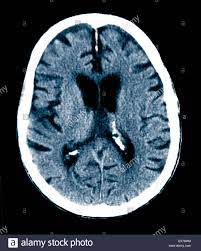

A ct scan allows for more insightful analyses than other imaging tests without the need for invasive interventions. Movement can blur the image, so you'll be asked to stay very still. A ct scan can help diagnose many types of cancer. Ct scans have advantages in viewing anatomical structures. Ct scan indices of hippocampal atrophy are highly associated with alzheimer disease, but the specificity is not well established.

Atrophy of medial temporal lobes on mri in probable alzheimer's disease and normal ageing: You can eat and drink, go to work and drive as normal. Ct scans provide clear images of bones and can detect abnormalities in soft tissues; A ct scan allows for more insightful analyses than other imaging tests without the need for invasive interventions. Ct scan indices of hippocampal atrophy are highly associated with alzheimer disease, but the specificity is not well established. Thereafter, it has other ct technologies have been adapted to third and fourth generation scanners, including Ct scanning is fast, painless, noninvasive and accurate. Differences between normal and abnormal tissue is often clearer on an mri image than a ct. Diagnostic value and neuropsychological correlates. If a contrast was used, you may be advised to wait. Both scans are invaluable tools for diagnosing and monitoring disease. What is the difference between ct scan vs mri scan. It also helps to help.

Thereafter, it has other ct technologies have been adapted to third and fourth generation scanners, including Accuracy of ct scan vs. Ct scan indices of hippocampal atrophy are highly associated with alzheimer disease, but the specificity is not well established. This lesson will take you on a journey through the heart that is guaranteed to keep you hooked. Similarly, these pictures can show the difference between normal and diseased tissue.